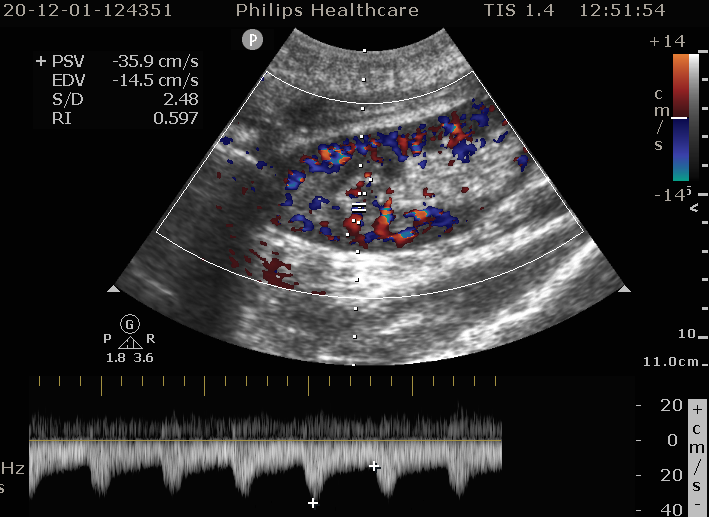

移植肾的超声表现 - 好大夫在线

图片尺寸709x517